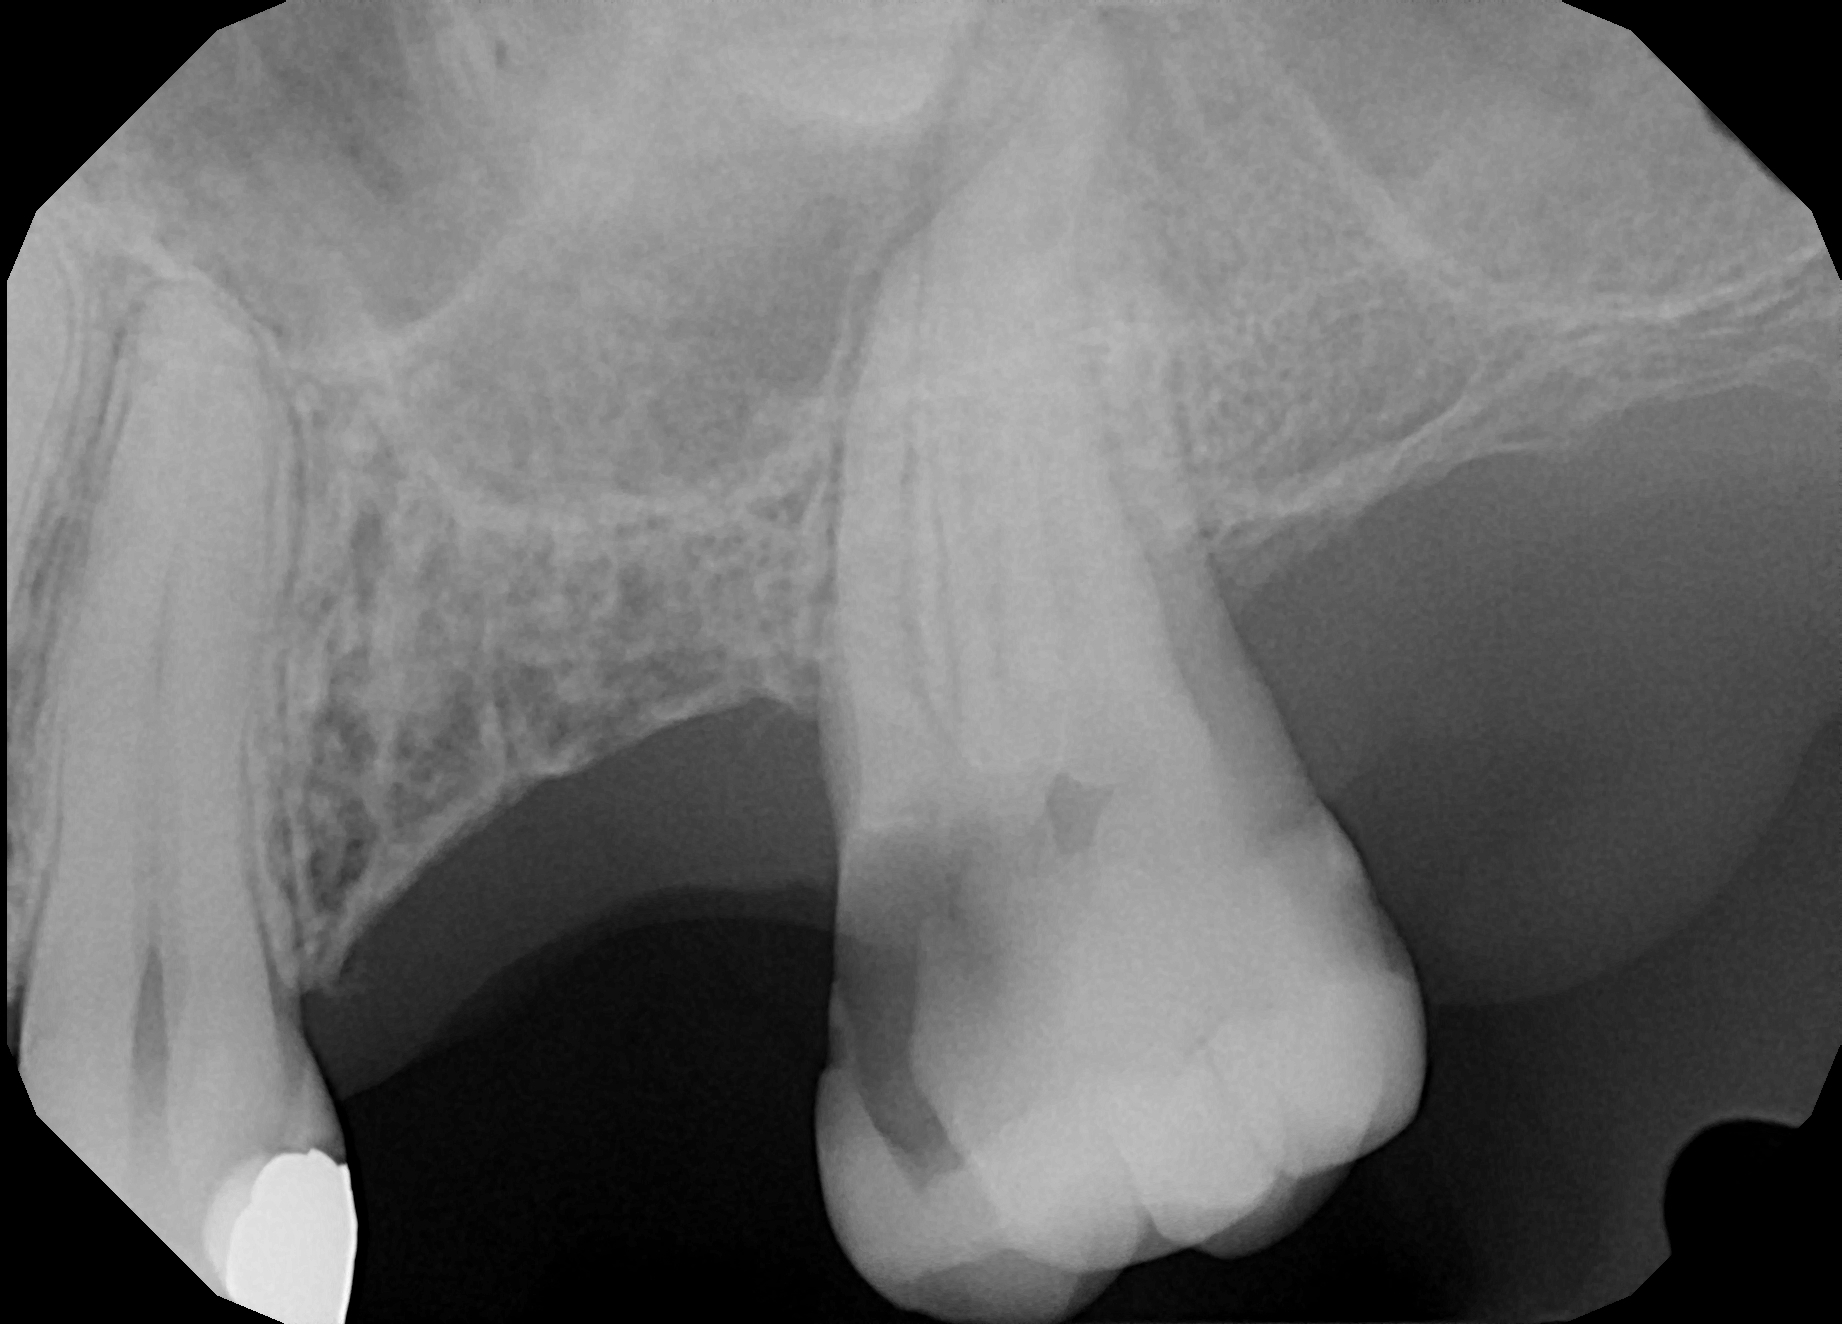

Fig.: 1

It is important to understand that when dentists work with rotary files, which typically rotates at approximately 300 rpm in the canal space, the flutes of the instrument are totally blocked just after the start of the motion. Therefore, most of the debris and cut dentine are packed into the lateral anatomy. This creates problems from the very beginning because of this blocking of already tight and narrow spaces, which are difficult to clean later. Improper instrumentation performed too fast with multiple strokes in one movement followed by lack of proper irrigation and activation leads to failures even when the radiograph shows beautiful white lines. We must not forget that anatomy is 3D (Fig. 1).